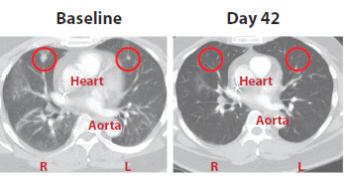

Per això, els nostres visitants del passat es posarien nerviosos i ens farien la pregunta clau: però, per què patim tuberculosi? En realitat, si el bacil de Koch és capaç de mantenir-se tant de temps als teixits és un problema relatiu . Hi ha molts virus que ja tenen aquesta propietat . El problema és que un 10 % dels pacients amb infecció latent pateixen la malaltia . I aquest no és el principal interrogant . . . En realitat hi ha un 50 o 60 % d’aquests casos en què es pot explicar per què s’ha desenvolupat la malaltia . Una immunodepressió ho fa possible, i depèn de la intensitat d’aquesta que hi hagi més o menys probabilitats que hi hagi aquest creixement baciŀlar i la destrucció de teixits que ocasioni un quadre clínic . Ara bé, hi ha un percentatge important que genera un tipus de lesió típica: la cavitat tuberculosa, paradigma clínic d’aquesta malaltia en l’adult . Paradoxalment, per generar aquesta lesió es requereix una resposta inflamatòria important . En aquest sentit el nostre equip fa anys que intenta entendre aquest procés més enllà del concepte clàssic d’infecció, basat en la presència d’una lesió antiga als lòbuls pulmonars superiors que ressuscita com a conseqüència d’un procés d’immunodepressió local (Cardona, 2009; Cardona i Ivanyi, 2011) . El que sembla clar és el tropisme del bacil pels lòbuls superiors, on hi ha menys irrigació capiŀlar, i això provoca no tan sols un increment en la concentració d’oxigen (a causa del menor intercanvi de gasos), sinó que a més hi hagi menys vigilància immunitària . D’aquesta manera sembla que, en actuar, el sistema immunitari veuria una concentració baciŀlar excessiva, fet que provocaria una resposta inflamatòria desmesurada (Cardona, 2011) . Però en la pràctica no tot és tan senzill, ja que hi ha un problema mecànic important: com

fer que una lesió de 0,5 mm es converteixi en una de 20 mm (vegeu la figura 2) . En aquest sentit som a les beceroles: encara no sabem per què es dóna aquest procés . Actualment, el nostre grup també està treballant activament en l’estudi d’aquest enigma, i almenys disposem d’un model experimental que permet reproduir la generació d’aquesta «superlesió» de manera satisfactòria, per la qual cosa en podem dissecar la fisiopatologia (Marzo, 2012) . Pels resultats preliminars, tot plegat sembla indicar que hi ha un tipus de resposta de l’hoste (per tant, una característica genètica) que provocaria una entrada de neutròfils més important de l’habitual, fet que ocasionaria a la vegada un increment en la formació de macròfags escumosos, que en ser drenats i permetre el recreixement baciŀlar interior a la perifèria de la lesió generaria l’engrandiment del granuloma en qüestió de dies (vegeu la figura 1) . Ara bé, també és cert que cal que hi hagi una acumulació local de diferents lesions per poder fer una lesió tan grossa (vegeu la figura 2) en qüestió de dies . Aquest aspecte es veuria afavorit als lòbuls superiors a causa de la menor irrigació capiŀlar que també ocasionaria menys drenatge de bacils cap als nòduls limfàtics . En tot cas, aquest mecanisme, encara en estudi, s’integra perfectament en el concepte d’«hipòtesi dinàmica» de la infecció latent, basada en la constant reinfecció endògena . Quan aquesta té lloc als espais pulmonars superiors, hi hauria la possibilitat que en donar-se aquestes particularitats (hoste predisposat i acumulació de lesions) es pugui generar aquest tipus de lesió tan gran, i així burlar els mecanismes de fibrosi i encapsulament de les lesions (vegeu la figura 1), que són molt potents a l’hora d’evitar l’engrandiment de les lesions (Cardona i Ivanyi, 2011) .

0,5 mm, d21 8 mm, d33 2 mm d30 1 mm d28

Figura 2. Inducció de les lesions cavitades. El gran interrogant de la inducció d’aquest tipus de lesions és com un granuloma de 0,5 mm es pot convertir en una cavitat de 20 mm (a). La resposta es troba en el model del ratolí C3HeB/FeJ. En aquest model en 21 dies s’indueixen les lesions de 0,5 mm; aquestes multipliquen la seva grandària per 2 en 7 dies, per 4 en 10 dies i per 8 en 12 dies. La conjunció de diverses lesions juntes fa que acabin desenvolupant-ne una de grossa de 20 mm (b).